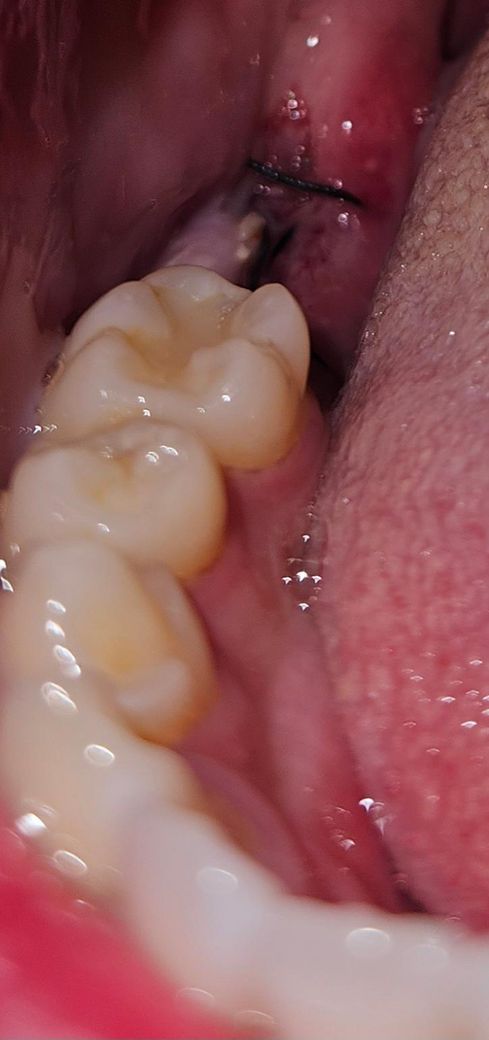

사랑니,어금니 2개발치 6일차인데 잇몸 염증인가요?

사진으로는 핑크색? 부위인데요 (조그만한건 음식물이겠죠..)

사랑니, 그앞어금니 2개를 발치했습니다

발치 부위는 별이상 없는거 같은데 왜 그 사이 벽쪽에 저런게 생긴건가요? 혀로 살짝 건드려보니 물컹해요

통증은 없는데 이물감이 있네요.

보통 하얀색으로 덮이는건 치유조직이라는데 저기는 발치부위가 아니라 걱정되네요

월요일에 실밥은 풀기로 했습니다.